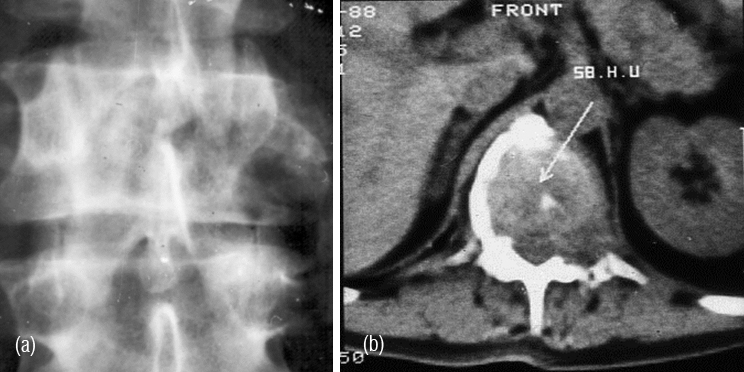

It is a solitary lesion and can be encountered in any bone. However, it is common in the spine. Most of the benign looking plasmacytomas when followed may develop into multiple myeloma eventually. Radiologically, a plasmacytoma is an expanding lytic lesion without any calcification or new bone formation. When it involves the vertebral body a compression fracture may be seen. When marked compression is seen vertebral plana is noted (Figure 1abc). To differentiate from metastasis, it is stated that in metastasis pedicles are involved earlier as they are vascular (2ab). However, when a large part of the body is involved in myeloma, pedicles also may be destroyed (Figure 3abc).

Figure 1a,b: Plasmacytoma with collapse of C3, T10. (c) Plasmacytoma – vertebra plana T8.

Figure 2: (a) Plasmacytoma of L2, (b) CT guided biopsy.

Figure 3abc: Plasmacytoma - Complete destruction of body of L3 including the posterior elements.